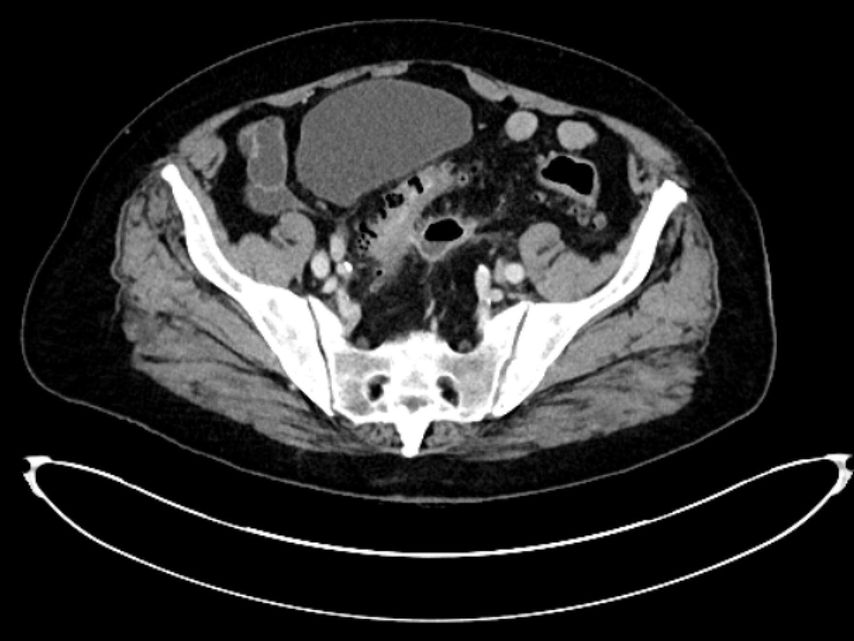

maladie diverticulaire/diverticulite simple aiguë (type 1a–b) (Fig. 1),

diverticulite compliquée aiguë (type 2a–c) (Fig. 2 et 3) et

Pour la classification de la diverticulite sigmoïdienne, la «Classification of Diverticular Disease» (CDD) s’est imposée (Tab. 1). Celle-ci a pour but de recueillir les différentes évolutions indépendamment d’une opération ainsi que de stratifier les différents pronostics et options thérapeutiques lors du premier diagnostic ou en cas de récidive. Une distinction est faite entre les formes suivantes:

La diverticulite compliquée aiguë de type 2 distingue, avec les types 2a et 2b, la perforation couverte avec micro-abcès (≤3cm) et macro-abcès (>3cm). Le type 2c désigne la perforation libre avec péritonite purulente ou fécale. La diverticulite compliquée aiguë nécessite une hospitalisation et doit être traitée par une antibiothérapie. Si l’apport en liquides est insuffisant, il convient de substituer les liquides par voie parentérale. Un apport alimentaire adapté à la situation peut être mis en place. Contrairement au macro-abcès de type 2b, le micro-abcès de type 2a n’est pas accessible au drainage interventionnel. Si le traitement est efficace, il n’y a pas forcément d’indication d’une opération élective. Il convient de noter que le risque de récidive est corrélé à la taille de l’abcès. Les abcès rétropéritonéaux ou péricoliques (>3cm) peuvent faire l’objet d’un drainage interventionnel. Après une thérapie conservatrice ou interventionnelle réussie de la diverticulite, une opération peut être proposée dans l’intervalle sans inflammation, après environ 6 semaines.